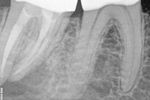

Revisionsbehandlung eines Unterkiefermolaren (37) vor geplanter Überkronung (Dr. Maik Göbbels) Download